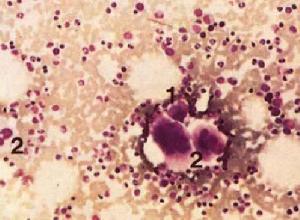

1.血小板減少,程度不一,常在30×109/L以下,偶可低於10×109/L。個別患兒血小板數可不降低。骨髓巨核細胞數正常或減少,白細胞正常。出血後可有貧血和網織紅細胞數升高,間接膽紅素升高。